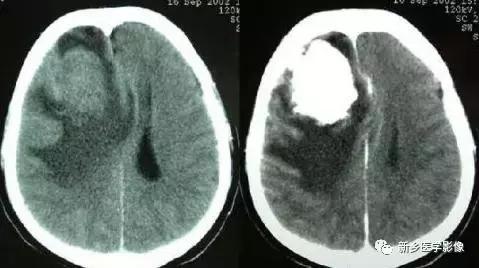

十一、特发性家族性脑血管铁钙质沉着症(Fahr’s病)

病理学上以双侧基底节区铁钙质沉积为特征。也可发生于丘脑、小脑齿状核和皮质下区。CT表现为双侧基底节区对称性钙化,呈均质较高密度,轻者钙化仅局限于苍白球、尾状核、壳核和丘脑,严重者大脑半球皮层下、小脑齿状核和脑回呈弥漫性广泛性钙化。